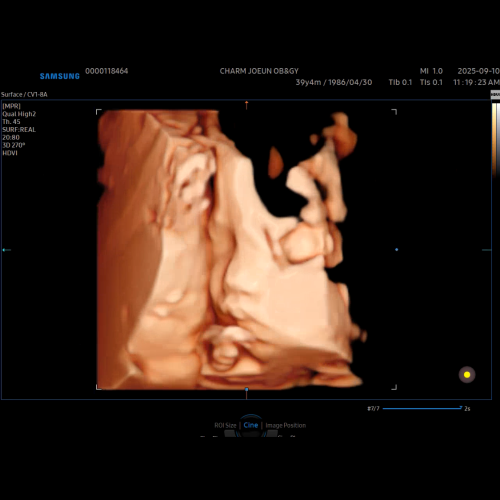

우리아가 첫모습!

벌써 중기에요. 콩알모양의 아가 모습이 엊그제 같은데요. ...